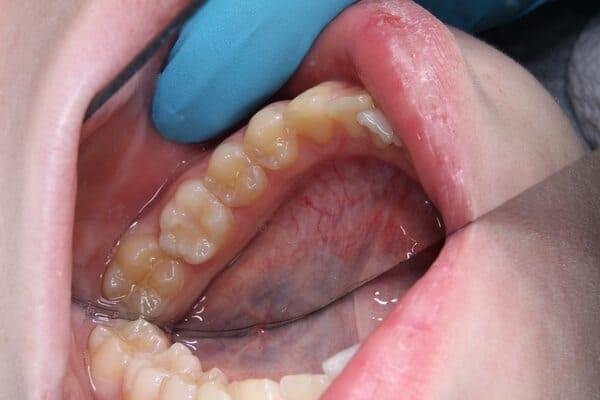

якщо зуб мудрості росте під нахилом, він може тиснути на сусідній зуб, спричиняючи його руйнування або стирання.

ці зуби можуть спричиняти постійне прикушування щоки та інший дискомфорт.